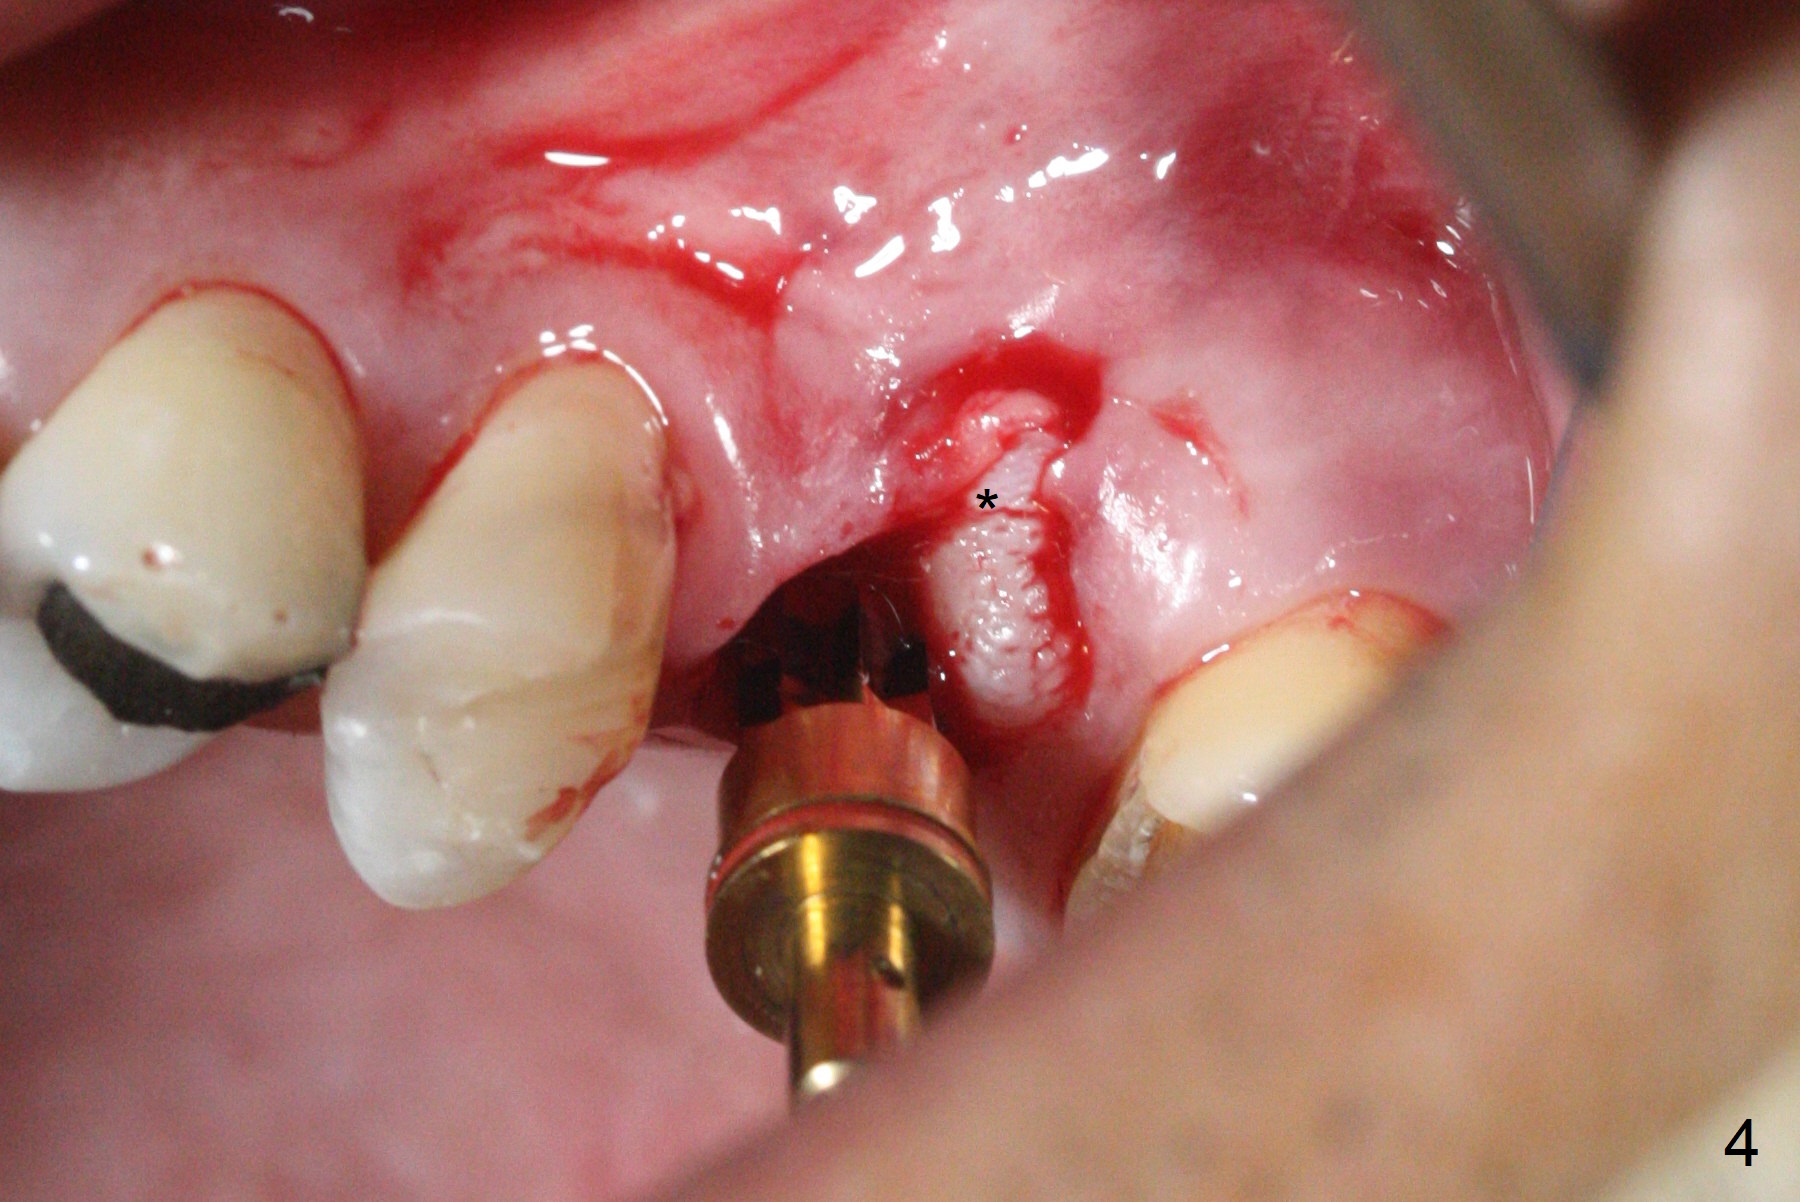

After extraction of the distobuccal residual root of the tooth #14 (Fig.1 arrow), the gingiva around the socket does not look like the keratinized one (Fig.2 *). An osteotomy through the distobuccal socket would seem too buccal for immediate implant. The palatal gingiva feels too tough to be stretched. An incision is made (Fig.3 dashed line); with elevation, the thick flap is transferred buccally (curved arrow). An osteotomy is initiated in the palatal bone with 1.5 mm drill, followed by Magic Expanders until 4.3 mm for 11 mm (Fig.4,5). Following Magic Drill 3.8x13 mm, the sinus membrane is found to be perforated. The latter is repaired with Osteogen plug. A 4.5x9 mm IBS implant is placed with 50 Ncm (Fig.6). Osteogen plug and allograft (Fig.7 *) are inserted into the remaining distobuccal socket (reduced after bone expansion). When a 5.5x4(4) mm abutment is placed, the transferred flap appears to be adapted to the distobuccal defect (Fig.8 *). Later one suture is placed for fixation. After provisional insertion, periodontal dressing is applied. Nine days postop, the periodontal dressing dislodges. When the loose provisional is removed for recementation, the flap seem to have healed (Fig.9 *). The gingiva heals around the abutment 5 months postop (Fig.9); the distal socket appears to heal while the bone graft remains at the crest (Fig.11,12). When #30 develops buccal abscess, the patient masticates on the left, leading to loss of composite at #13 (Fig.14); in fact the abutment at #14 is incompletely seated.